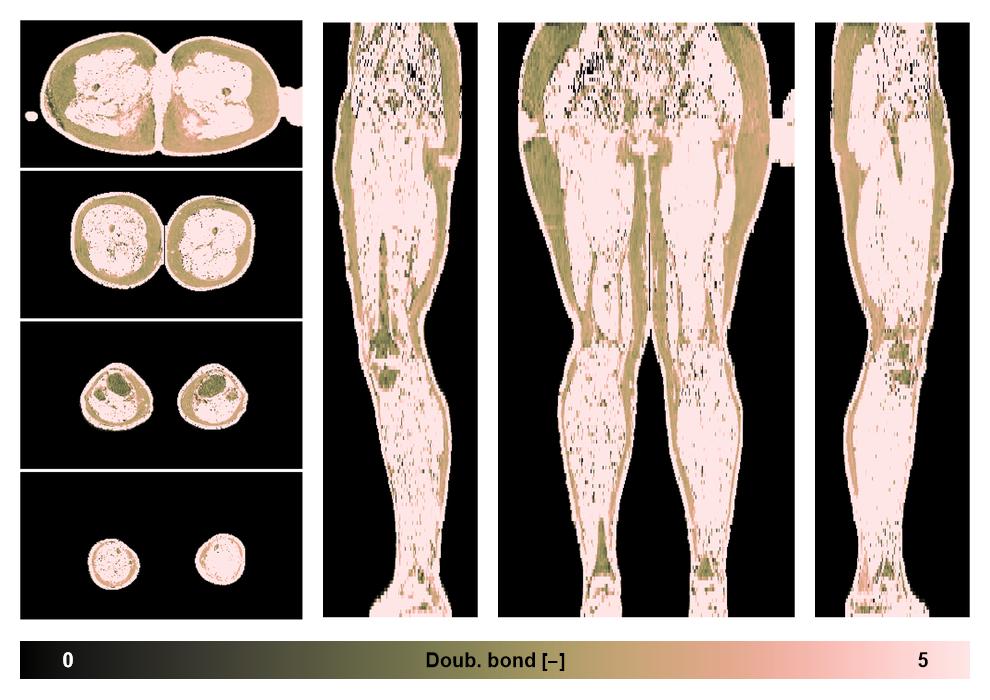

• Number of double bonds in subcutanious fat

Number of double bonds in subcutanious fat.